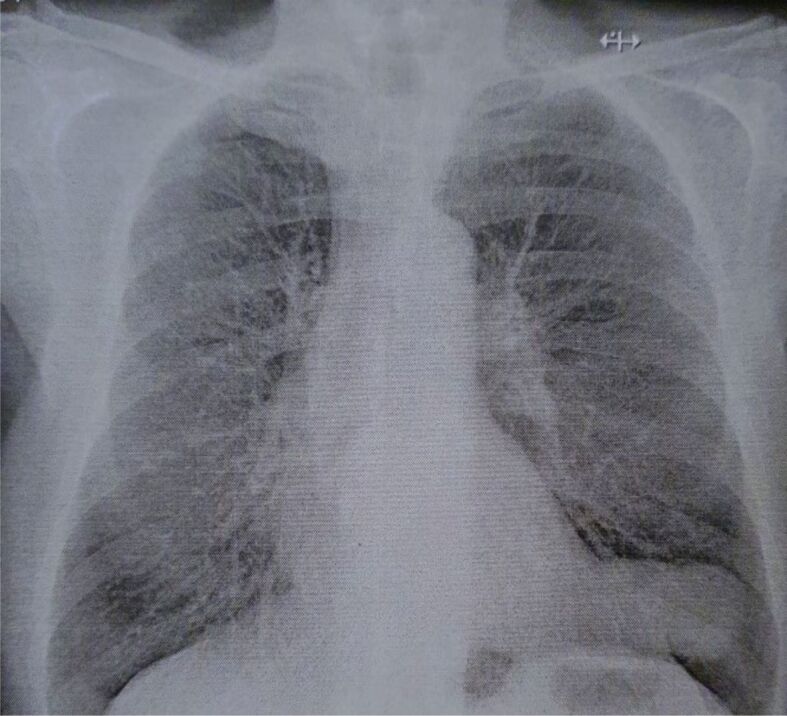

心包囊肿(PCs)或胸膜心包囊肿是一种罕见的先天性纵隔病变,发病率约为十万分之一。它们通常没有症状,是在常规胸部成像检查或尸检时偶然发现的。本研究对在罗马尼亚雅西肺病诊所接受治疗的 6 年系列 PCs 的临床病理结果进行了回顾性评估。共评估了五例肺结核患者,其中四例为女性,一例为男性。所有患者均表现出不同的症状,如呼吸困难、胸痛、慢性咳嗽、疲劳、心悸和上腹痛。四例患者的囊性病变位于左右心膈角,一例患者的囊性病变位于中央纵隔。病灶中含有液体,最大直径在 35 至 95 毫米之间。手术切除组织的显微镜检查显示,结缔组织壁很薄,没有任何相关的平滑肌细胞。疏松的结缔组织带内衬一层无细胞不典型性的间皮细胞,其中一例显示出离散的乳头状突起。虽然 PCs 是罕见的偶然发现,但在纵隔囊肿的鉴别诊断中应考虑到它们,尤其是当它们与非特异性症状相关时。此外,考虑到PC可能会引发严重的并发症,因此应彻底检查PC,以便对患者进行适当的治疗。

Pericardial cysts (PCs) or pleuropericardial cysts are rare congenital mediastinal lesions with an approximate incidence of one in 100 000 persons. Usually, they are asymptomatic, being incidentally discovered during a routine chest imaging examination or an autopsy exam. The study involved a retrospective evaluation of clinicopathological findings in a 6-year series of PCs, treated in the Clinic of Pulmonary Diseases, Iaşi, Romania. A group of five cases of PCs, four females and one male, were evaluated. All patients displayed different symptoms, such as dyspnea, chest pain, chronic cough, fatigue, palpitation, and epigastric pain. The cystic lesions were located in the right and left cardiophrenic angle, in four cases, and in the central mediastinum in a single case. The lesions had a fluid content and a maximum diameter that ranged between 35 and 95 mm. The microscopic examination of the surgical resection tissues revealed a thin connective tissue wall without any associated smooth muscle cells. The loose connective tissue band was lined by a layer of mesothelial cells with no cellular atypia, which displayed discrete papillary projections, in one case. Although PCs are rare incidental findings, they should be considered in differential diagnoses of mediastinal cysts, especially as they are associated with non-specific symptoms. Furthermore, considering the possibility of development of severe complications, PCs should be thoroughly explored for suitable patients' management.